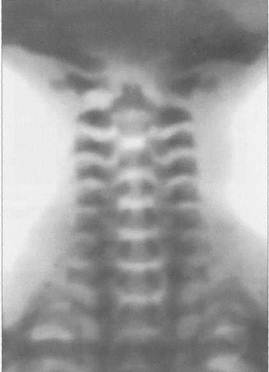

Позвоночник состоит из 24 позвонков, крестца и копчика. У здоровых людей он образует характерные физиологические изгибы: кпереди в шейном и поясничном отделах и кзади в грудном и крестцовом. Величина тел позвонков постепенно увеличивается в каудальном направлении, т.е. книзу (рис. Ш.203). Тело позвонка на рентгенограммах имеет форму прямоугольника с несколько вогнутыми боковыми гранями и закругленными углами. Смежные горизонтальные площадки тел позвонков образуют на рентгенограммах четкий широкий контур (второй контур обусловлен одним из краев тела позвонка). Спереди позвонок опирается на межпозвоночный диск, а сзади — на два межпозвоночных сустава — своеобразный трехсус-тавной комплекс.

г JUL Ш - 203 - Обзорные рентгенограммы поясничного отдела позвоночника и «семы позвонков в прямой (а) и боковой (б) проекциях.

- поперечный отросток; 2 - межпозвоночный диск; 3 — остистый отросток; тело позвонка; 5 — верхний суставной отросток; 6 - корень дуги позвонка- 1 — нижний суставной отросток.